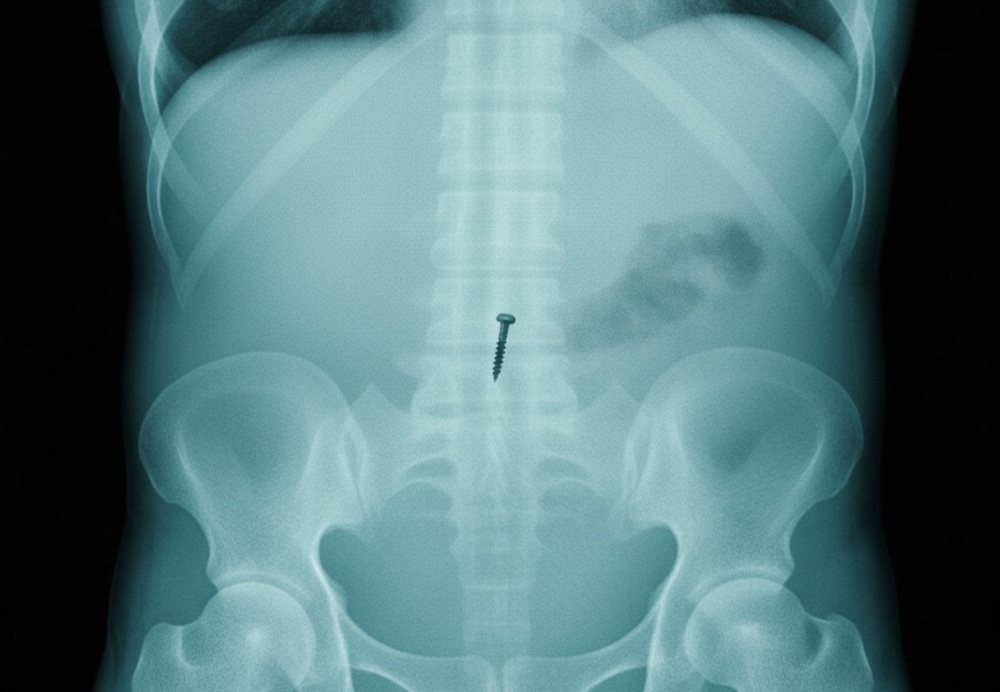

На прошлой неделе мать мальчика заметила неладное и привезла его в стационар через час после инцидента. Рентген подтвердил: внутри организма находится острый металлический предмет. Врачи решили достать саморез с помощью эндоскопа, не делая разрезов.

Медики обнаружили инородное тело на входе в двенадцатиперстную кишку. В этой опасной ситуации пациенту очень повезло: саморез шёл по организму шляпкой вниз, остриём вверх. Благодаря этому он не проткнул стенки желудка и кишечника. Врачи подтянули его обратно в желудок и вытащили.